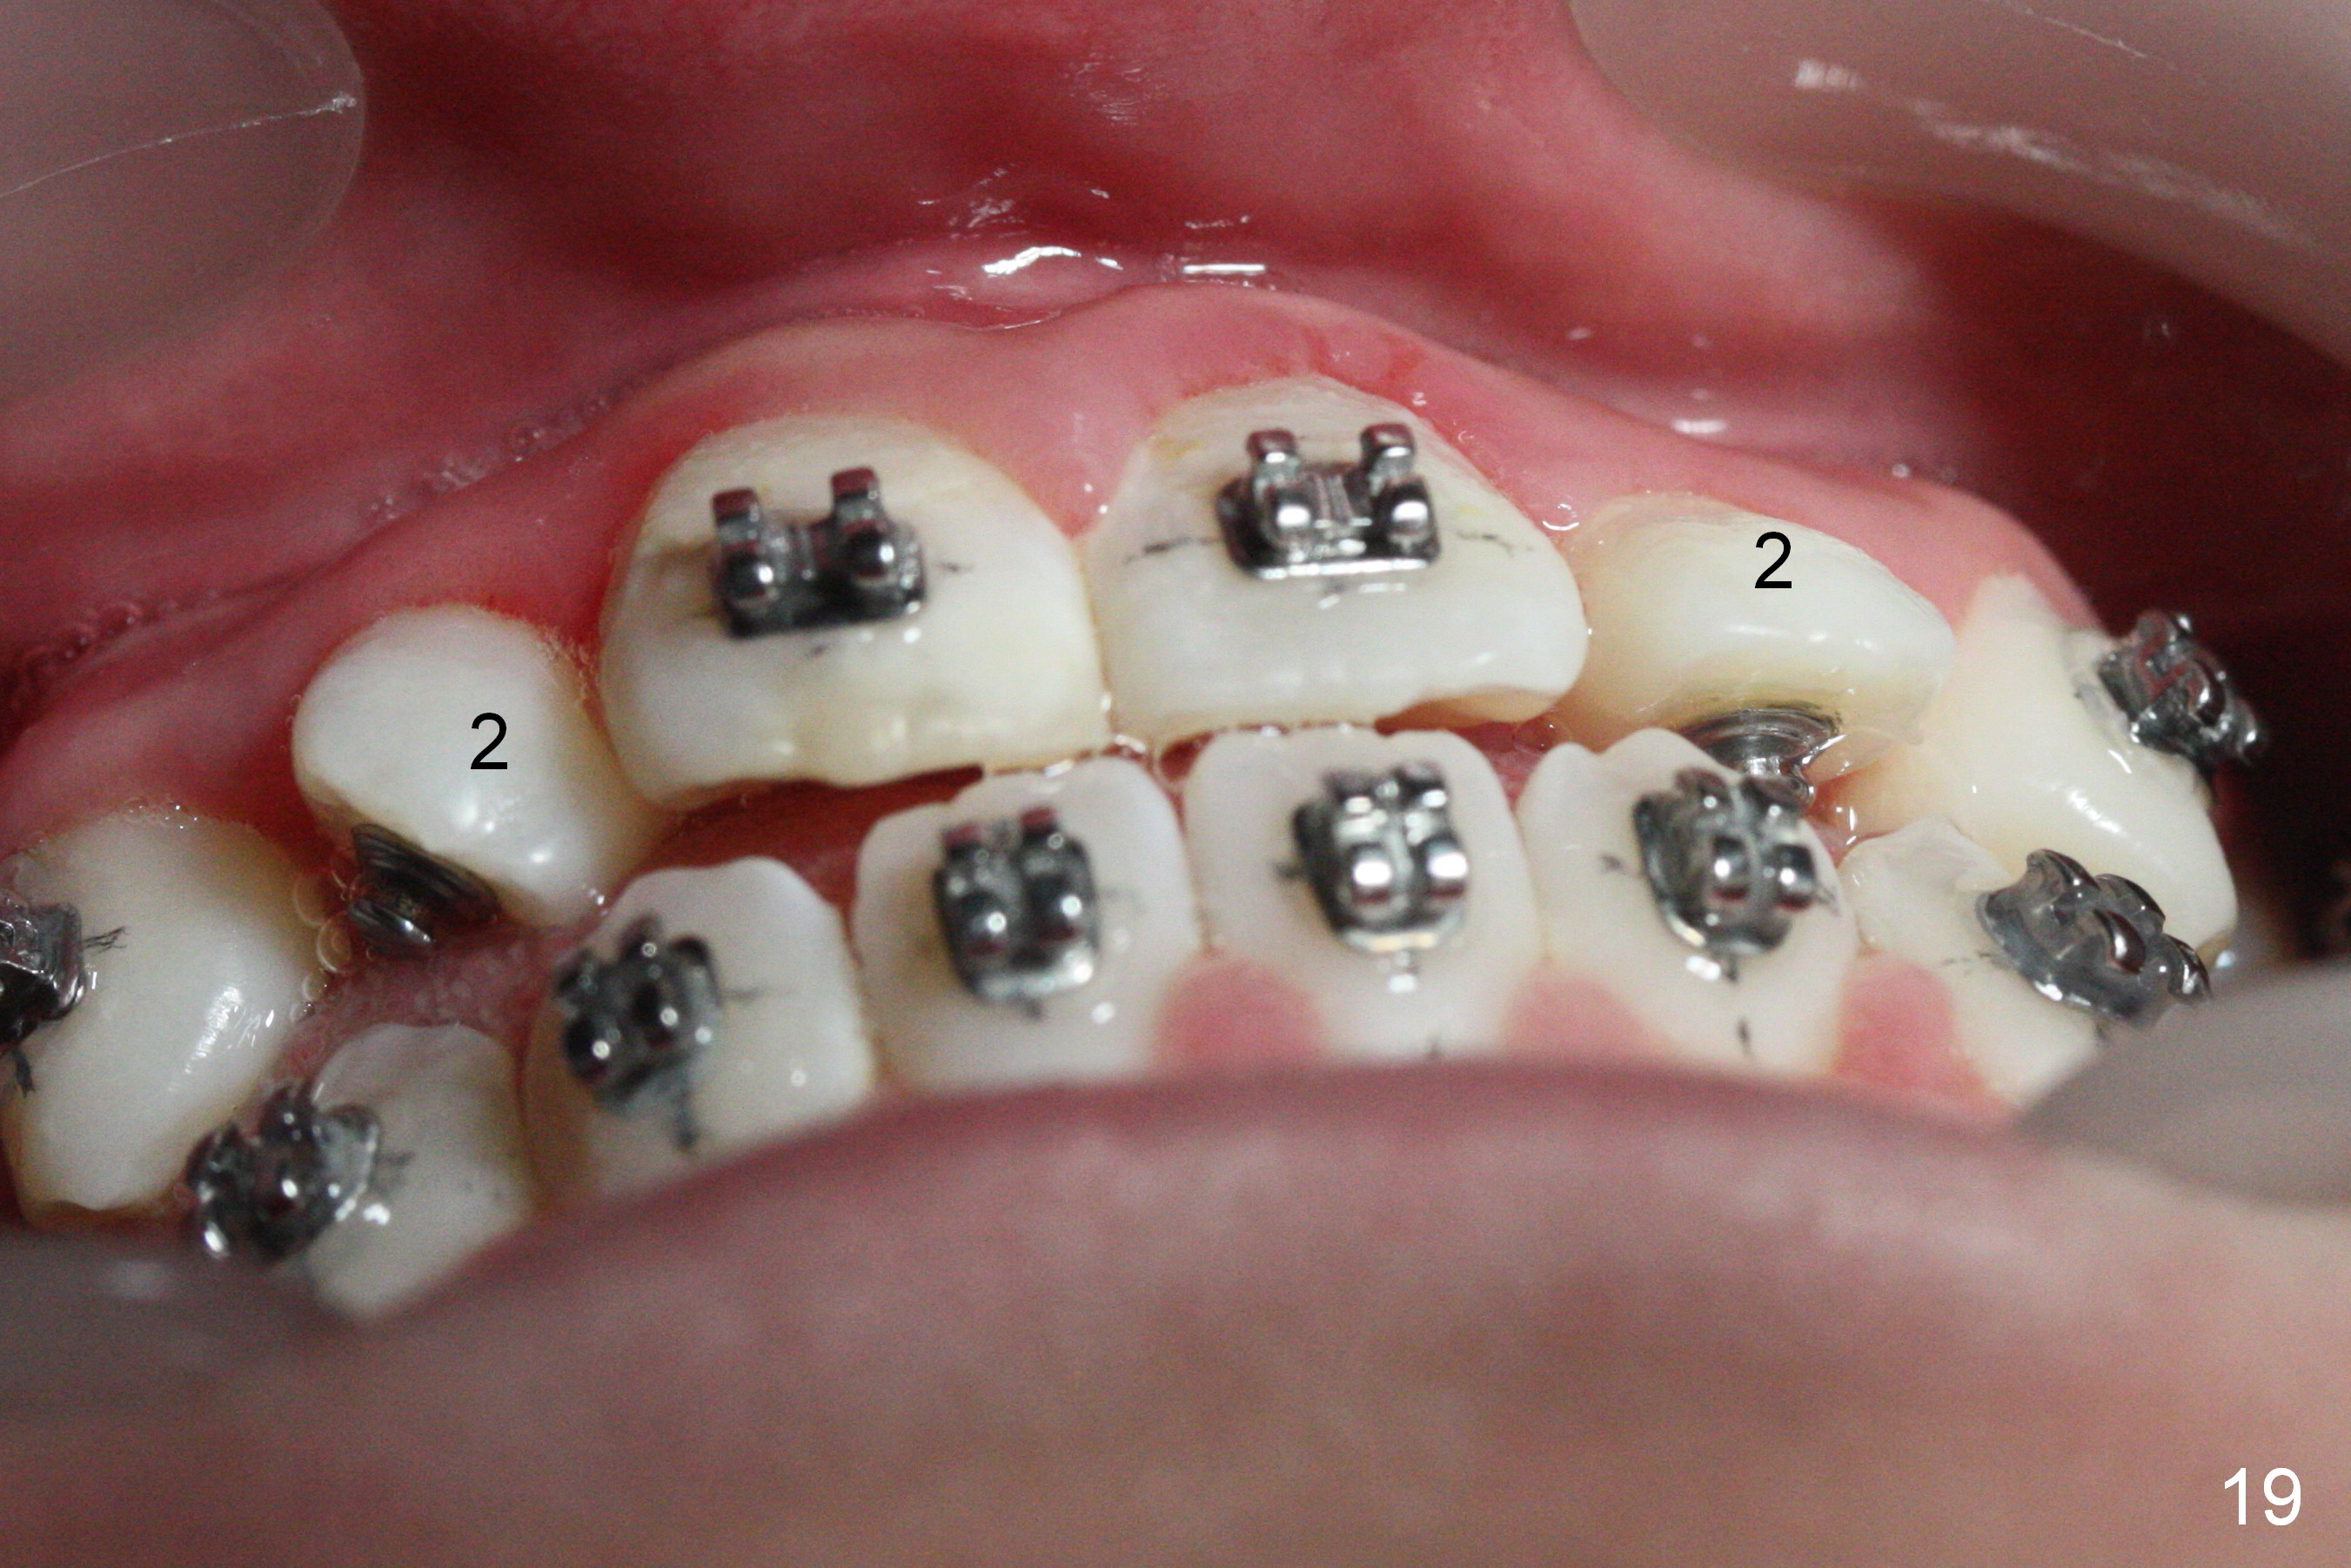

Three visits after open coil spring and 1 visit after sling shot, U2 cross bite is corrected (Fig.18,19). Due to UR2 rotation (Fig.19), bracket cannot be placed (Fig.20, 16 niti). Power chain x 3 is placed between UR2 and 3 to gain space for bracketing, which turns out not working. UL2 bracket is placed upside down for torque.